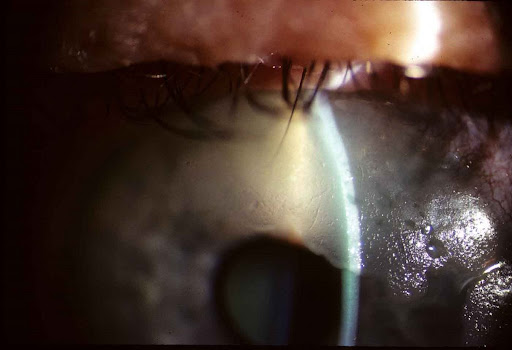

각막상피의 투명도가 없어지면서 유백색의 병변으로 상피의 혼탁이 관찰되며,

주로 각막 상피만을 침범합니다.

치료는 긁어내거나 각막윤부를 포함한 광범위 절제로 가능하나,

표층 각막 절제술을 시행시 보우만막을 제거하면 혼탁이 더 심해지므로 주의해야합니다.